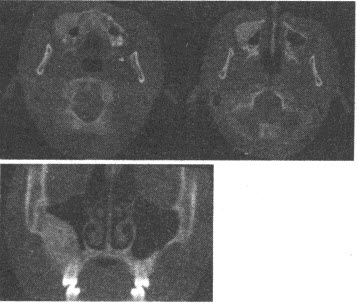

患者,女,38岁,头痛、头晕、耳鸣2年,一侧肢体活动不利近1年。CT平扫示:右侧中后颅窝卵圆形略高密度灶,边缘锐利,右侧岩骨尖,骨质变薄;MRI示T1WI呈等信号,T2WI呈高信号;CT及MRI增强扫描呈均一强化。

第1题,共3个问题

(单选题)最需与本病例进行鉴别的疾病是()

A:三叉神经瘤

B:胶质瘤

C:听神经瘤

D:脑淋巴瘤

E:脑脓肿

第2题,共3个问题

(单选题)本病例最为可靠的MRI影像特征是()

A:牛眼征

B:胡椒盐征

C:靶征

D:脑膜尾征

E:灯泡征

第3题,共3个问题

(单选题)本病例最有可能诊断为()

A:听神经瘤

C:脑膜瘤

D:三叉神经瘤